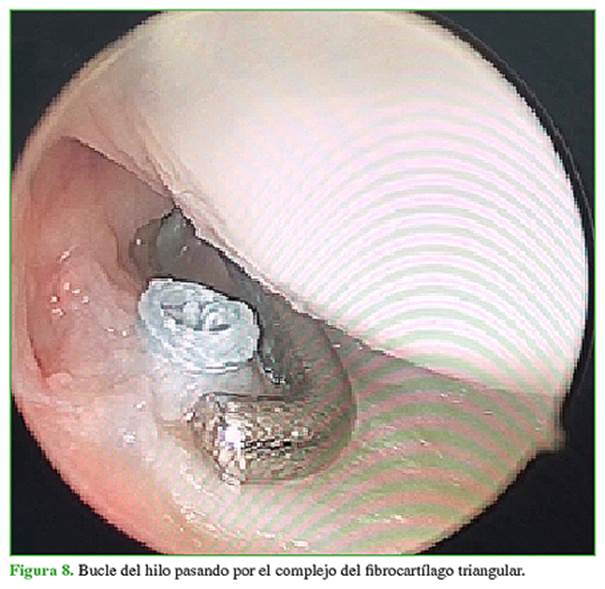

Se procede a la sinovectomía y el desbridamiento de la lesión (Figura 2). A continuación, se coloca la guía del CFCT por el portal 6R y bajo visión ¾, se coloca la guía en la zona 2/2 descrita por Matsumoto (Figura 3). Se efectúa un abordaje cubital de 2 cm para colocar la guía al mismo tiempo que se la posiciona por el portal 6R y se coloca una clavija por la guía hasta salir en la articulación y asegurarse de estar en la zona 2/2. Se fresa con una guía de 3.0 desde el cúbito hasta la articulación. Al finalizar se retira la guía y se coloca por el orificio cubital un pasador de hilo 2.0 tipo fiberwire penetrando el disco; se retira ese hilo por el portal 6R sin perderlo por el túnel cubital (Figuras 4-6). A continuación, se coloca un pasador de hilo con un rescatador de sutura por el túnel cubital penetrando el disco 2 mm a volar o dorsal y se retira el rescatador de sutura por el portal 6R (Figuras 7-9). Se pasa el hilo por el rescatador de sutura y se tira desde el rescatador de sutura por el abordaje cubital siempre mirando desde portal ¾. Se observa cómo la sutura pasa hacia el orificio cubital tensando el fibrocartílago (Figuras 10-12). Mediante un dispositivo de anclaje sin nudo de 2,8 mm se colocan las dos puntas de los hilos dentro del sistema de fijación y se lo impacta 5 mm distal al túnel realizado (Figuras 13 y 14). Se comprueba que las pruebas del trampolín y del gancho sean negativas, se retira la tracción y se prueba la estabilidad. Se cierran los portales. Se coloca una férula tipo Munster (pinza de azúcar) por cuatro semanas con movilidad de dedos y hombro, y luego, se inicia el programa de rehabilitación. Las primeras dos semanas se realiza con férula corta ballenada de muñeca de uso permanente, solo se retira la férula en rehabilitación y dentro de la casa para una movilidad controlada de la muñeca. Luego de las seis semanas, se usa la férula rígida de muñeca por la noche únicamente y se indica la movilidad enérgica de la muñeca libre sin carga. A las ocho semanas, se comienza con la fuerza progresiva y se retira, en forma definitiva, la muñequera.